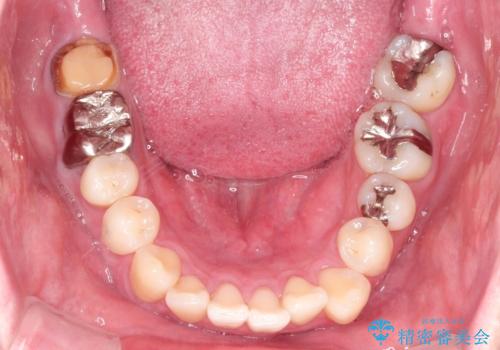

全体的ながたつきをインビザラインで改善

- 全体的ながたつきを主訴に来院されました。

歯と歯の間をわずかに削って、スペースをつくり並べる計画としました。

しっかりと、マウスピースの装着時間を守っていただいたので、スムーズに治療をおえることができました。